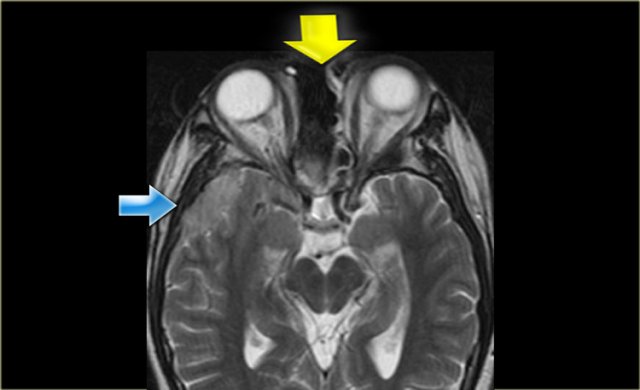

Lymphoma of sphenoid sinus and skull base Lymphoma of sphenoid sinus and skull base

Coronal images of the same patient: T1 pre-and post-contrast.

Normal aspect of the right Meckel's cave, tissue in the left Meckel's cave extending into the cavernous sinus (blue arrow).

The red arrow points to the dural margin of the cavernous sinus: there is enhancement on both sides of the dura.

The disease wraps around the temporal lobe (green arrow) and extents downward in the foramen ovale (yellow arrow) and into the masticator space.

The asterix indicates normal non-enhancing tissue in the masticator space.

This patient had a lymphoma.

Nine out of ten times an immunocompromised patient will have a fungal infection, in one out of ten it will be a lymphoma.

CT and MR have a complimentary role in this case, but finally a biopsy is called for to differentiate between these two diagnoses, because of different treatment.